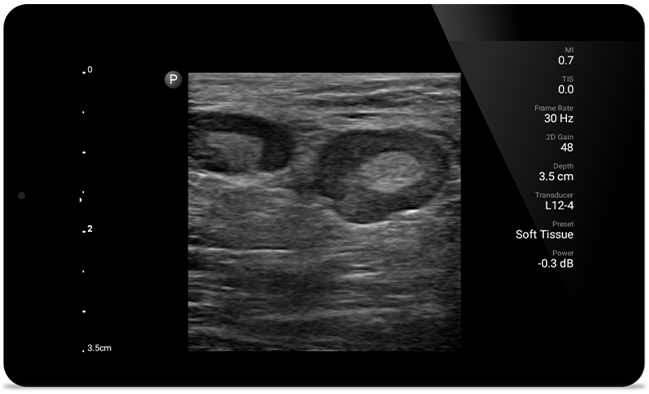

Lumify helps you see the fine details in muscles, joints, ligaments, tendons and cartilage to make a more accurate diagnosis of injuries.

Lumify can help you assess patients from head to toe, whether it’s plantar fasciitis, tendonitis or bursitis in the patellar tendon, or even shoulder instability in the rotator cuff.

SonoCT reinforces real tissue imaging while eliminating random artifacts. This technology produces images superior to conventional imaging in up to 94% of patients.